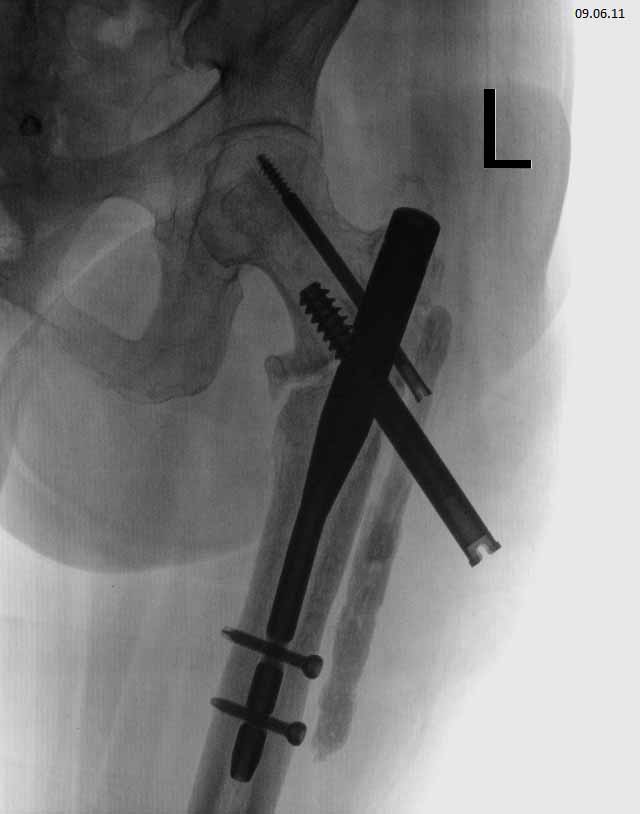

Чрезвертельный перелом левого бедра, в результате ДТП. Женщина 56 лет, ДТП. Чрезвертельный перелом. Было выполнено: скелетное вытяжение- 1 месяц, остеосинтез Г- образной пластиной (Россия), через 4 месяца второй остеосинтез, через 4 месяца вылез винт, выполнена операция- удален один винт, аллопластика. Наложена кокситная повязка. Через 2,5 месяца: щель перелома прослеживается на всем протяжении, склероз по краям отломков. Болей нет. Посоветуйте, что делать дальше, к кому и куда обратиться за помощью. Проживаю в СПб.

Сейчас конструкция несостоятельная. Надо в любом случае ее удалять и заменять на другую, чтобы обеспечить немедленную возможность ходьбы с нагрузкой без риска смещения. Времени на лечение уже ушло в несколько раз больше обычного.

У нас в отделении сейчас делается довольно много операций по такого рода поводам. Предпочли бы сделать остеосинтез стержнем. Есть модификации, исключающие миграцию, подобную случившейся. Делать какие-то пластики и вообще широко обнажать кость не видно необходимости. Возможно, будет целесообразно увеличить шеечно-диафизарный угол.